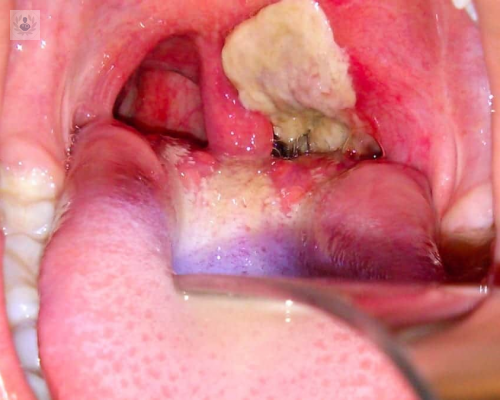

Fiebre de origen desconocido

La Fiebre de Origen Desconocido se diagnostica cuando ésta es superior a 38.3°, durante más de tres semanas y sin causa aparente. Supone un reto para el medico internista y requiere una Exploración Clínica minuciosa.